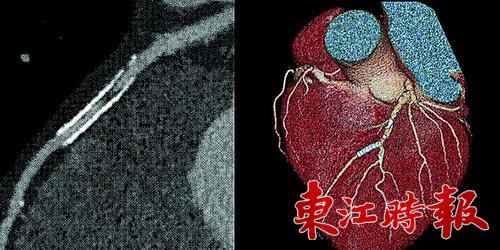

但是寶石能譜CT,卻可以不受金屬影響成影。不要小看這個(gè)功能,它帶來的卻是多種多樣的CT新應(yīng)用?;葜菔械谌嗣襻t(yī)院醫(yī)學(xué)影像科主任醫(yī)師崔冰告訴記者,有的冠心病患者曾植入過支架,有的骨頭受損傷的患者,身體內(nèi)植入了鋼釘,對面這些類型的患者,由于身體內(nèi)有金屬,再想通過常規(guī)CT來觀察是不太可能了,而磁共振也無法很好的解決這一問題。過去,醫(yī)生們只能用最為傳統(tǒng)的方法,了解病人恢復(fù)是否理想來判斷內(nèi)部情況?,F(xiàn)在使用寶石能譜CT,就可以通過成影直接看到患者植入鋼釘?shù)牟课?,如果出現(xiàn)問題,醫(yī)生能夠更加及時(shí)地發(fā)現(xiàn),并對患者加以治療。

“有一位60歲的患者,不愿開刀,就接受了寶石能譜CT檢測?!贝薇Q這位男性患者自稱胸悶,伴有其它病史,對插管較為抵觸。經(jīng)過寶石能譜CT檢測,醫(yī)生在該患者的動(dòng)脈里發(fā)現(xiàn)血栓已有部分鈣化,并有管腔狹窄?!靶卵捎盟幬锟刂坪腿芩?,老血栓只能用支架撐開血管了?!贝薇硎?,常規(guī)CT只能顯示血栓,但是寶石能譜CT可以反映出新、老血栓,根據(jù)新舊的不同,采取的治療方法也不同。如今該患者的病很快就得到了確診,正在進(jìn)行下一步的治療。